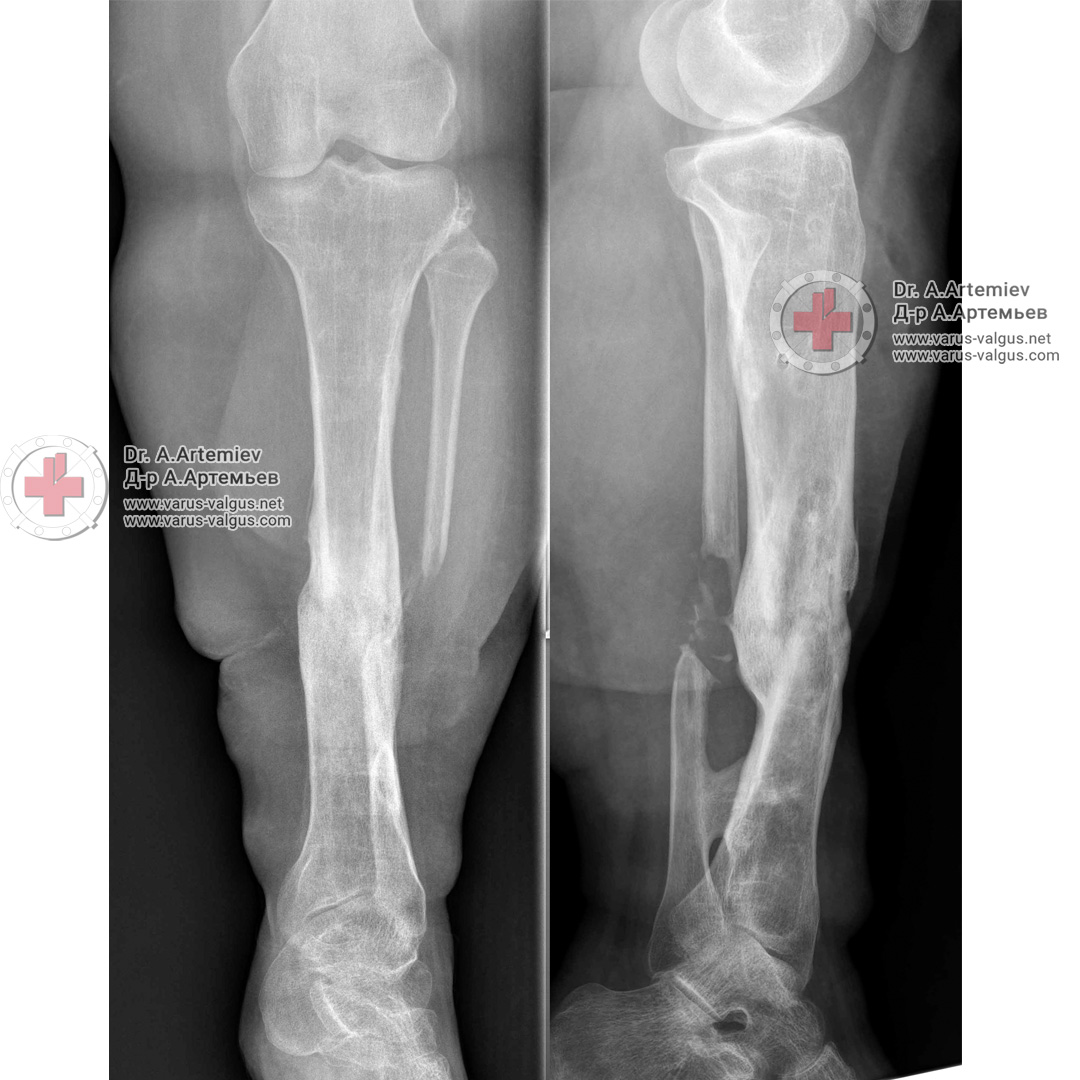

ПОСТТРАВМАТИЧЕСКОЕ УКОРОЧЕНИЕ ГОЛЕНИ + НАРУЖНАЯ РОТАЦИЯ + ВАЛЬГУС (1-Й ЭТАП КОРРЕКЦИИ)

Девушка 18 лет. Получила травму несколько лет назад в результате падения с высоты. После нескольких операций голень срослась с укорочением 11 см, вальгусной деформацией и наружной ротацией.

Первым этапом удлинили левую голень на 5,5 см и устранили деформацию. При значительном укорочении не следует пытаться удлинить ногу сразу на большУю величину. Можно столкнуться с серьезными проблемами. Лучше разбить лечение на несколько этапов. В данном случае мы решили первым этапом удлинить на 5-6 см и исправить имеющиеся деформации. Первый этап лечения длился 7 месяцев.

После периода реабилитации, если пациентка решит продолжить лечение, удлиним ещё на 5 см.